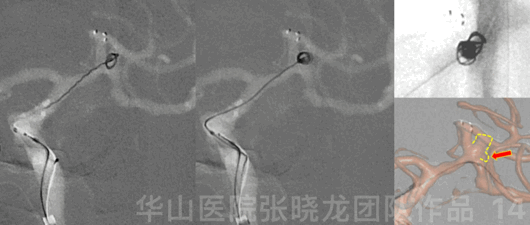

图 13 GIF. 重新选择工作角度,于瘤颈部部分释放Solitaire 4*20mm支架。直头Echelon-10微导管在微导丝导引下通过瘤颈部后轻轻回撤,微导管置于瘤腔。这过程中,3D路途显示子瘤。

图 14. 填入Target helical ultra 3mm*6cm弹簧圈。

图 15 GIF. 选用另一根直头Echelon-10微导管置于大脑中动脉下干。经栓塞微导管填入一枚Target helical ultra 2.5mm*4cm弹簧圈后完全释放Solitaire支架。然后继续填入4枚弹簧圈( Perdenser 2d 2.5*8, Target 360 ultra 2*4, 2枚Target 360 ultra 2*3 )。

The lobular aneurysm had multiple daughter sacs, which could not be fully revealed on one working projection. These daughter sacs should be monitored via the 3D roadmap during superselection.

The stent was not fully deployed, in order to advance the coiling microcatheter easier.

分叶状动脉瘤有多发子瘤,单个工作角度不能将其显示清楚。超选择造影时应通过3D路途清楚显示这些子瘤。

为了栓塞微导管超选方便,一开始不完全支架释放。